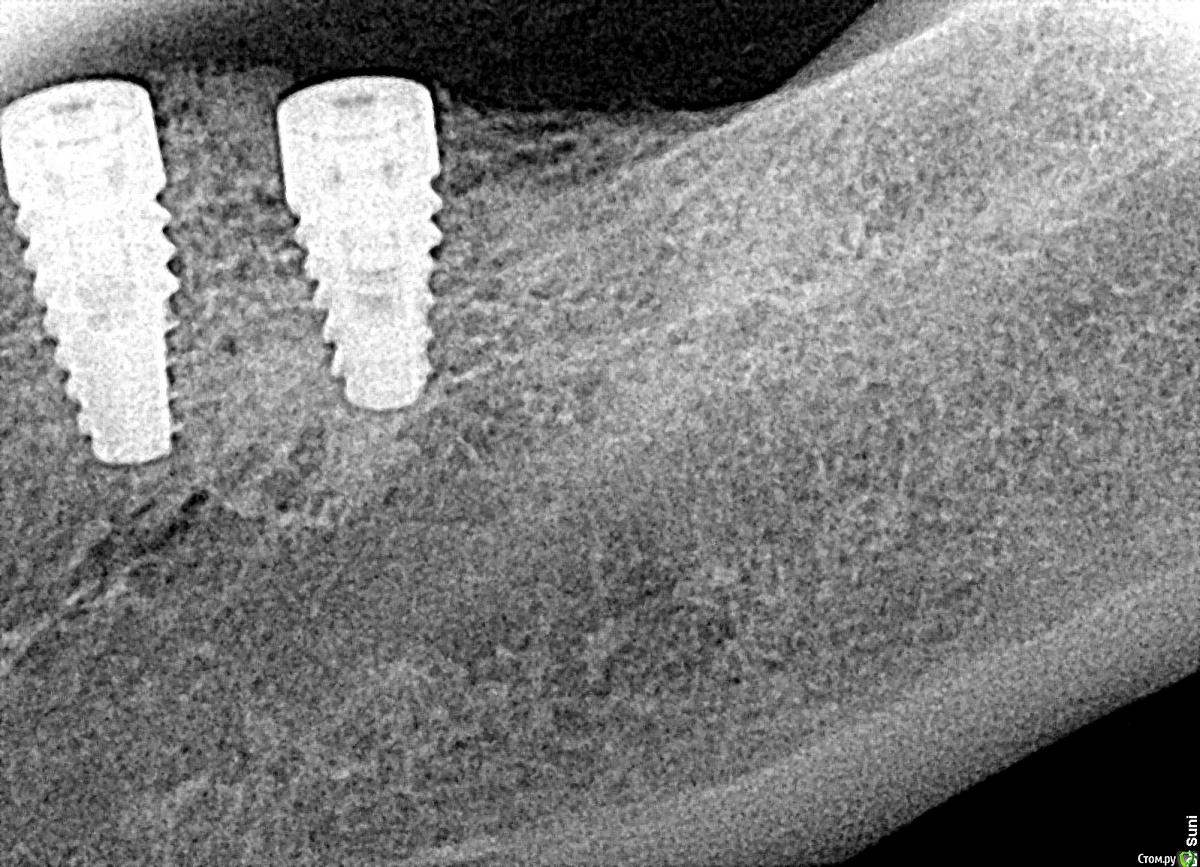

bilal Опубликовано 25 декабря, 2017 Поделиться Опубликовано 25 декабря, 2017 добрый день. 2 месяца назад ставил 6 имплантов на нижней челюсти, сегодня сделал рентген, вокруг шейки двух имплантов такая картина.может надо было изначально заглубить побольше.как вы думаете, кокой прогноз? и какие дальнейшие действия? у дального импланта просвечивала заглушка, ставил фдм. Ссылка на комментарий

bilal Опубликовано 25 декабря, 2017 Автор Поделиться Опубликовано 25 декабря, 2017 снимки на момент имплантации и сегодня Ссылка на комментарий

kamranchick Опубликовано 25 декабря, 2017 Поделиться Опубликовано 25 декабря, 2017 Прогноз благоприятный. дальнейшие действия должны быть направлены на улучшение качества мягких тканей 3 Ссылка на комментарий

колесников Опубликовано 25 декабря, 2017 Поделиться Опубликовано 25 декабря, 2017 Такое случается в участках давней адентии. Отслоили ,ушили-потеряли по гребню как минимум 1мм. К сожалению в Вашем случае ремоделировка не закончена. В любом случае надо улучшать биотип слизистой. Добавьте сст с бугра,это зачастую благоприятно влияет на подлежащую кость. Ссылка на комментарий